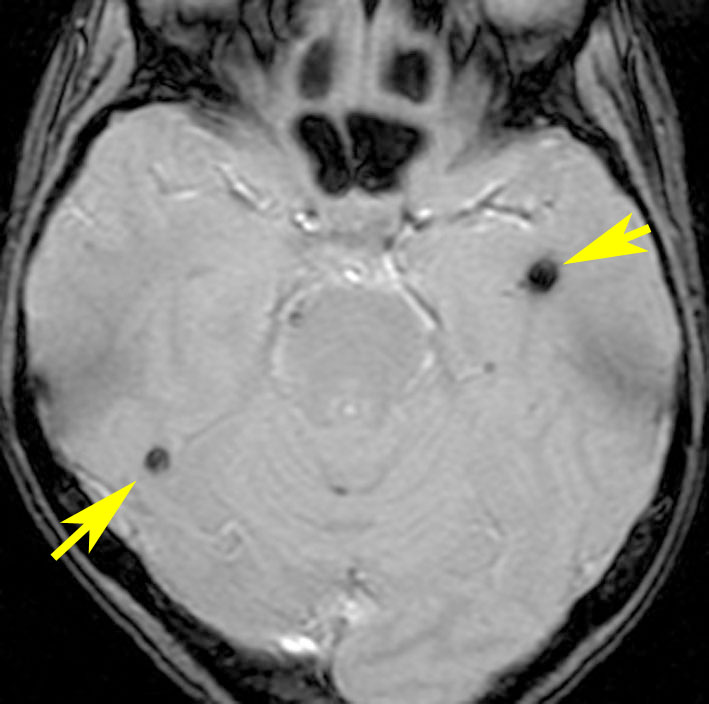

- T2スターというMRI画像で発見できます

11歳の時に全脳室照射24グレイ・12分割を受けた女の子です。10年以上経過して,脳のあちこちに小さな黒い点状のものが見えるようになってきました。これは子供の頃に放射線治療を受けた人に多く,なんでもないもので症状は出ませんし,ほっておいていいものです。微小な脳静脈の放射線損傷による血液の漏れだと考えられています。

- 低信号(黒いシミみたいなもの)として脳内たくさん見られることがあります

- これは血液の中の鉄分が脳に滲み込んだ形跡をみているものです

- だから,海綿状血管腫とは言わないで,blood leak(血液が漏れた痕跡)と読んだ方がいいものです